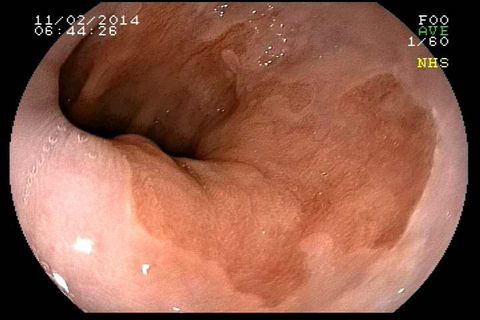

O que é Esôfago de Barrett?

Esôfago de Barrett é uma doença na qual há uma mudança anormal na mucosa do esôfago distal. A doença é causada principalmente pela exposição prolongada ao conteúdo ácido proveniente do estômago e está relacionado a um risco aumentado de câncer do esôfago. Esôfago de Barrett ocorre quando as células normais da porção inferior do esôfago são substituídas por um tipo diferente de células (semelhantes às do estômago). O Esôfago de Barrett normalmente é causado pelo refluxo gastroesofágico (RGE). Portanto, esta substituição das células do esôfago pelas células do estômago, muitas vezes é vista como um mecanismo de proteção ao ácido (as células do estômago são preparadas para resistir à acidez). É importante salientar que a maioria das pessoas que tem RGE nunca desenvolverão o Esôfago de Barrett, mas algumas podem desenvolver.Quais são os sintomas do Esôfago de Barrett?

Como detectar o Esôfago de Barrett?

O diagnóstico de Esôfago de Barrett é feito através da endoscopia digestiva alta com biópsia da área suspeita. O médico vai examinar com detalhes a região da transição entre o esôfago e o estômago e, se houver a suspeita de um epitélio anômalo na região, serão coletadas biópsias para análise no microscópio. A inspeção do Esôfago de Barrett deve ser realizada por endoscopista experiente e com aparelho de alta definição, para capturar detalhes suspeitos da mucosa.

Qual o risco do Esôfago de Barrett virar câncer?

Uma complicação do Esôfago de Barrett é que, com a agressão contínua do ácido no epitélio do esôfago, podem surgir células pré-malignas (displasias) que eventualmente podem crescer e virar um câncer invasivo. Estas lesões pré-malignas não costumam provocar sintomas, daí a importância de um acompanhamento médico. No entanto, a progressão do Barrett para um câncer é bastante incomum. Estudos que seguiram pacientes com Esôfago de Barrett, mostram que o risco de progressão para câncer é menor do que 0,5% ao ano.Como o Esôfago de Barrett é tratado?

Tratamento do Esôfago de Barrett com Radiofrequência

A ablação por radiofrequência usa calor para remover tecido pré-cancerígeno do esôfago de Barrett. A tecnologia do sistema de ablação por radiofrequência é projetada para a remoção de tecido afetado por Barrett, preservando o tecido saudável subjacente.Tratamento do Esôfago de Barrett com Mucosectomia

A mucosectomia é uma técnica empregada para ressecção do Esôfago de Barrett com lesões displásicas visíveis (pré-cancerígenas ou cancerígenas iniciais). Geralmente essa ressecção é realizada através da colocação de ligaduras elásticas, seguido da apreensão e corte com alça de polipectomia. O produto da ressecção é enviado para a análise histológica pelo patologista, a fim de verificar se o paciente está curado e para definir como será o acompanhamento no futuro.O que é gastrostomia endoscópica?